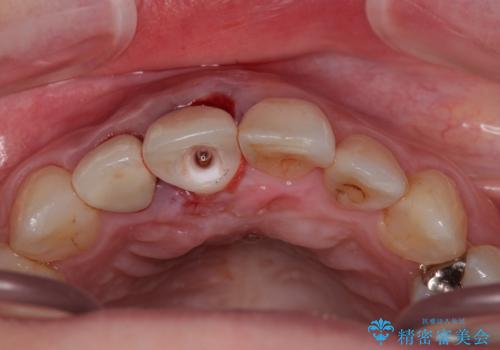

- 前歯のセラミッククランが外れてしまったとのことで来院された患者様です。

診察をしたところ、歯根に縦破折が認められ、抜歯が必要と判断されました。

抜歯、インプラント埋入、仮歯の装着が同時に可能な1DAYインプラントが適用可能と判断されたため、インプラントによる補綴治療を行うこととしました。